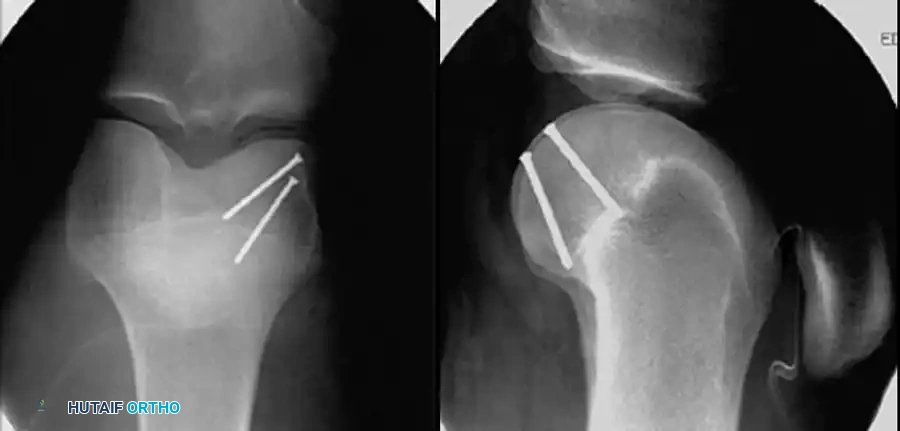

Image

Fig. 51-76 A, Anatomy and surgical exposure. B and C, Intraoperative posteroanterior and lateral radiographs demonstrating successful screw fixation of the posterolateral condyle. (From Taitsman LA, Frank JB, Mills WJ, et al: Osteochondral fracture of the distal lateral femoral condyle: a report of two cases, J Orthop Trauma 20:358, 2006.)